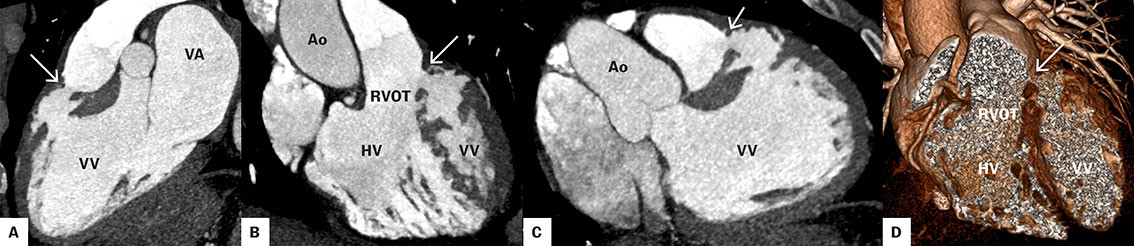

Pasientens alder, funn ved koronarangiografi og klinisk presentasjon gav mistanke om en postinfarkt ventrikkelseptumruptur og ikke en medfødt defekt. For å bedre kartlegge anatomien av defekten ble det gjort en EKG-gatet computertomografi (CT) av hjertet i arteriell kontrastfase. Undersøkelsen påviste en anteroseptal defekt på < 1 cm i ulike plan, med kontrastpassasje mellom venstre ventrikkel og høyre ventrikkels utløpskanal (figur 3). CT-undersøkelsen viste også refluks av kontrast til vena cava inferior og levervener som tegn på høyresidig hjertesvikt (ikke vist i figur). Pasienten ble innlagt fra poliklinikken samme dag og ble neste dag overflyttet til universitetssykehus for videre utredning.